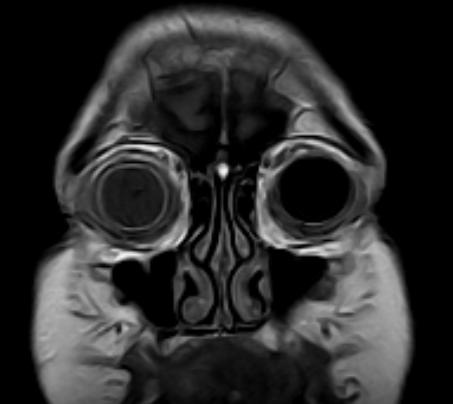

Se solicitan además ESTUDIOS COMPLEMENTARIOS

ECOGRAFÍA OCULAR

Informe: se observa buena esfericidad de ambos globos oculares. Músculos extra oculares y nervios ópticos de grosor conservado. Grasa del cono orbitario sin alteraciones.

OD: Opacidad de cristalino y engrosamiento coroideo con desprendimiento de retina.

OI: Engrosamiento coroideo, se observa retina aplicada.

Resonancia nuclear magnética de cerebro y órbitas, con y sin gadolinio

Informe: aumento de espesor de la esclerótica en el globo ocular derecho, que pone en evidencia un probable proceso inflamatorio. Sutil alteración en la posición del cristalino. Cambio de intensidad de señal a nivel del humor vítreo.